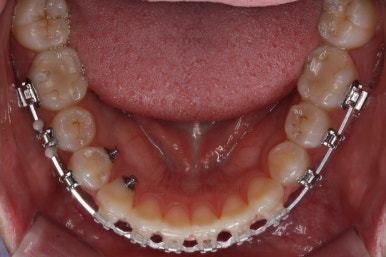

장치를 부착한 직후츼 사진입니다.

장치를 따라 걸려있는 철사의 형태를 보면 생각보다 많이 틀어져 있었구나 하고 느껴지게 되실거에요.

이번에 부착한 장치는 엠파워 클리어라고 하는 자가결찰 세라믹장치 입니다.(아마 이 장치 나올 때마다 설명드리는 것 같은데) 매우 유명한 클리피씨라고 하는 장치와 같은 컨셉의 장치입니다.

단지 제조 회사가 다를 뿐이죠.

(엠파워는 미국장치, 클리피씨는 일본장치)

술자의 선호도에 따라 장치가 선택되는데 클리피씨 보다는 부산치아교정잘하는곳인 키다리아저씨치과에서는 엠파워를 약간은 더 선호하고 있습니다.